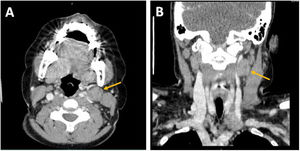

Debido a la persistencia de adenopatías, se solicita una tomografía computarizada (TC) en la que se observan múltiples adenopatías laterocervicales de predominio izquierdo en áreasII, III, IV yV cervicales, de consistencia sólida y de tamaño patológico (fig. 1). Además, se realiza una ecografía cervical para valorar las características de dichas adenopatías, también sugestivas de patología (fig. 2).